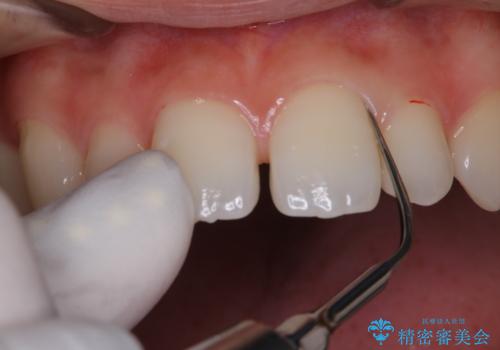

一見きれいに見える歯でも、染め出し(歯垢染色液)を使うとこのように歯と歯茎の境目や、歯と歯の間などに磨き残しがあることがわかります。歯磨きには、いつも気をつけているから磨き残しはナシと思っていても、実際完璧に磨ききることはなかなか難しいです。歯科医院にて、専門の機械で定期的なPMTCを行うことが大切です。